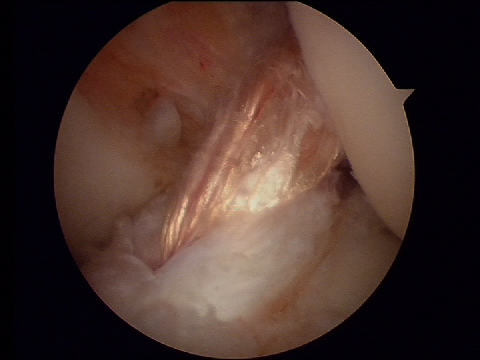

Nous réalisons depuis plusieurs années en première intention, une technique combinée en utilisant comme prélèvement autologue les tendons ischio jambiers.

La reconstruction combinée du LCA et du LAL a été décrite par le Dr Bertrand Sonnery Cottet (Santy Lyon). Cette technique permet une reconstruction biologique du LCA en préservant les fibres tibiales du LCA (technique SAMBBA) associée à une reconstruction anatomique du LAL.

Le LAL a été décrit récemment comme un ligament permettant de contrôler l’accélération de rotation du tibia ou le pivot.

Le Dr Betrand Sonney Cottet a prouvé dans ses publications que cette technique combinée permettait un meilleur retour au sport avec moins de risques de rupture itérative que les autres plasties ligamentaires (KJ ou DIDT).